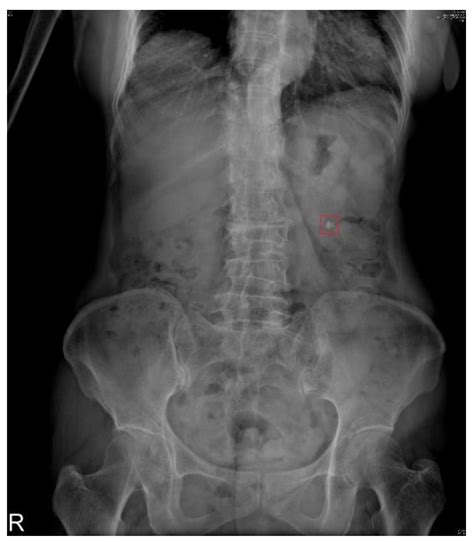

Diagnosis is usually confirmed through imaging. A non-contrast CT scan is considered the gold standard for identifying the exact location and size of the stone. A physician will evaluate the stone’s position—whether it is in the kidney, the upper ureter, or the lower ureter—as this drastically changes the treatment plan.